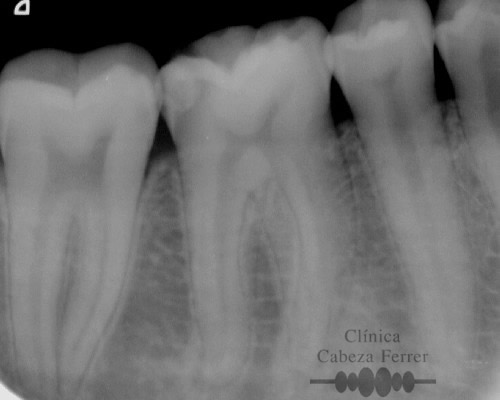

En primer lugar se explora la pieza y se realiza un estudio radiológico. Si es necesario se pone anestesia local y se aísla en diente para mantenerlo limpio y seco durante el tratamiento. A continuación con el instrumental adecuado se realiza un orificio en la corona del diente y a través de él, mediante unos pequeños instrumentos llamados LIMAS, se extrae la pulpa. Posteriormente la cámara pulpar y los conductos radiculares se limpian, se esterilizan, se rellenan y se sellan herméticamente. Con un control radiológico se comprueba que el tratamiento se ha realizado correctamente. Ahora es el momento de reconstruir la anatomía del diente y si es necesario recubrirle con una corona para evitar su posterior fractura. En la mayoría de los casos, la endodoncia se realiza en una sola sesión.

La endodoncia rotatoria avanzada es una novedosa técnica de instrumentación mecanizada que se realiza con un tipo de limas especiales de níquel-titanio. El auge del níquel-titanio surgió en la década de los sesenta, al ser utilizado por la NASA, principalmente en la fabricación de antenas de naves y satélites espaciales. Es este material, el que impulsa el desarrollo de los sistemas rotatorios en endodoncia. Estos instrumentos tienen la característica de de ser muy flexibles, por lo que pueden trabajar dentro de los conductos radiculares impulsados por un motor de baja velocidad, ejecutando una rotación de 360º hasta en los conductos curvos. De esta manera se combina la instrumentación manual convencional con la mecanizada consiguiendo así un resultado final con alta precisión, mejor limpieza, irrigación y terminación de los conductos, menos fracasos y unas restauraciones más duraderas.